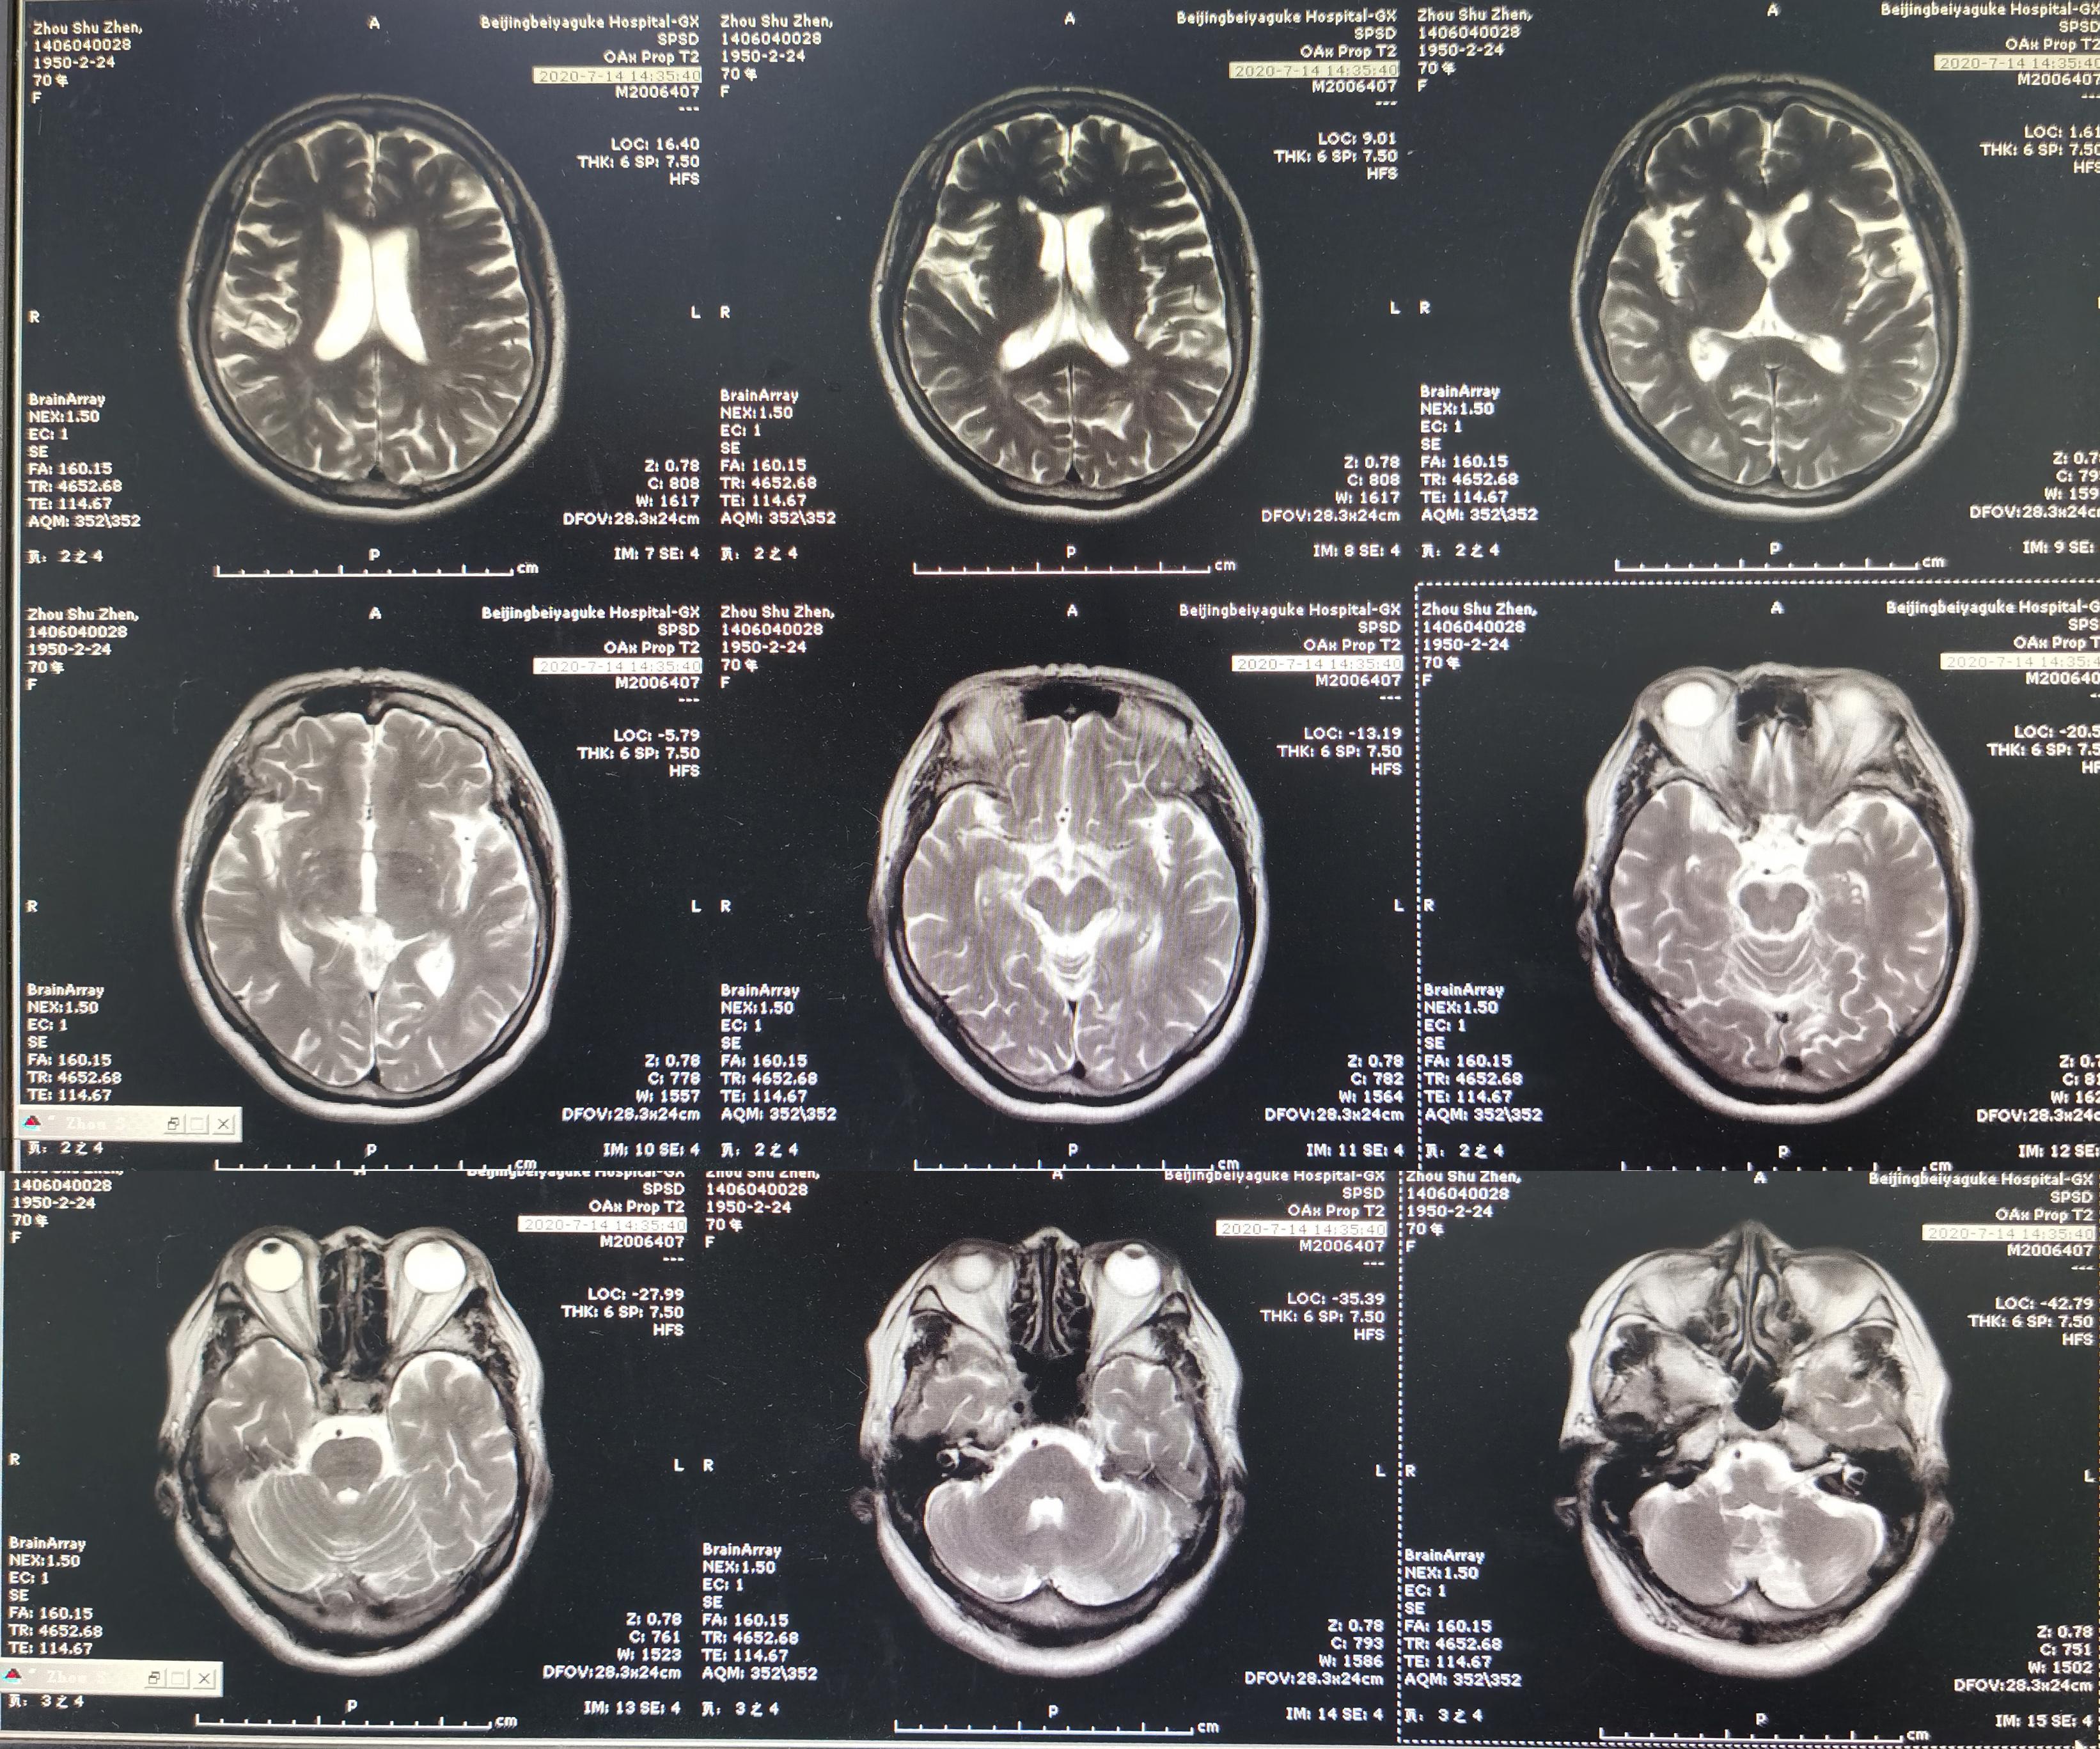

2020年7月14日(即第一次颈椎病术后83天)患者又出现头晕加重,尤以低头扭头时明显(注:患者未按照医嘱佩戴颈托),而且双上肢放射痛,麻木再次出现,双下肢无力,行走不稳,门诊复查头颅MR示小脑陈旧性梗塞( 图-4 )。

图-4: 2020年7月14日头颅MR